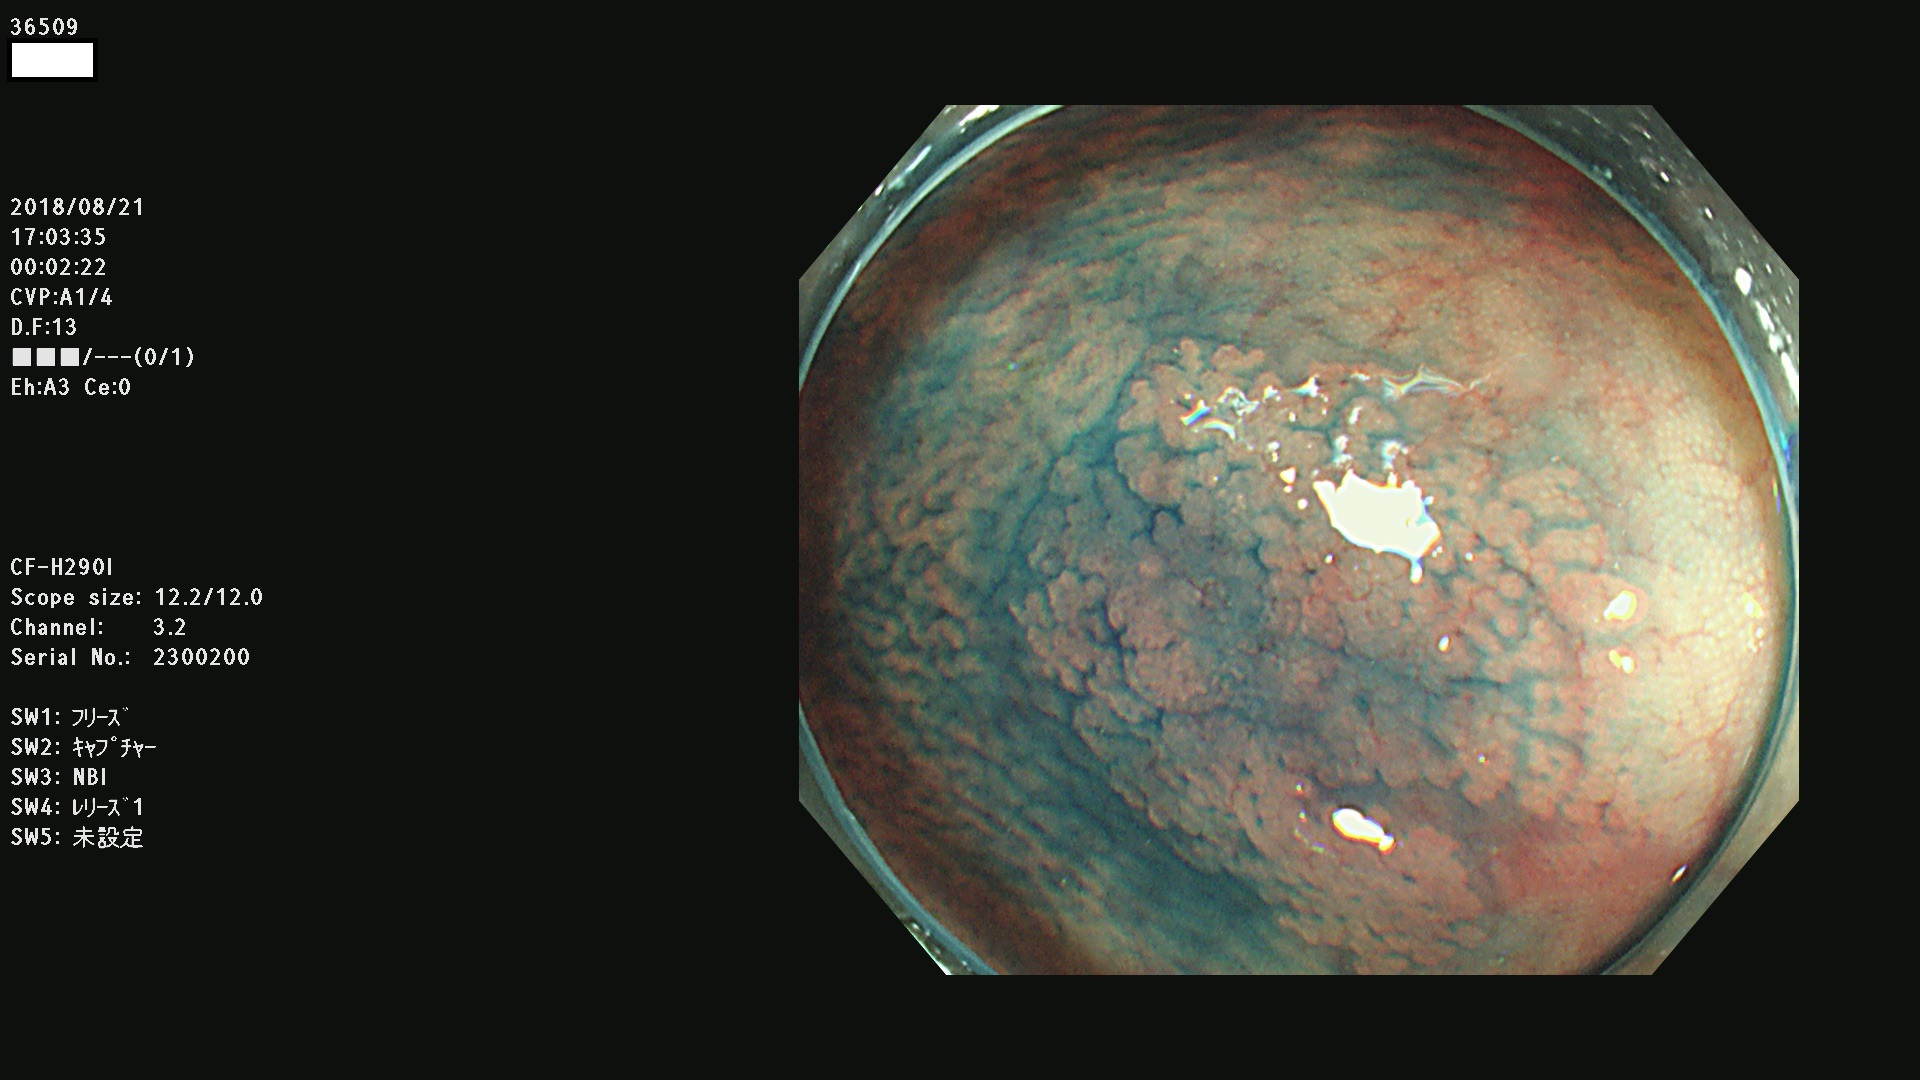

36500 36503 36504 36505 36507(SSAPのみ) 36508 36509 36510 36511 36514 36515 36517 36518 36520 36522(SSAPのみ) 36523 36524 36526 36528 36530 36531 36532 36533 36534 36535 36536 36538 36541 36542 36543 36544 36545 36546 36548 36550 36551 36554 36555 36556 36558 36559 36560 36561 36564 36565 36567 36568 36570 36572 36573 36574 36575 36576 36577 36578 36579 36580 36582 36584 36586 36591 36592 36593 36594 36595 36596 36597 36598

発見困難で危険性の高い平坦型病変(上記100名より抽出)

虫垂SSAP